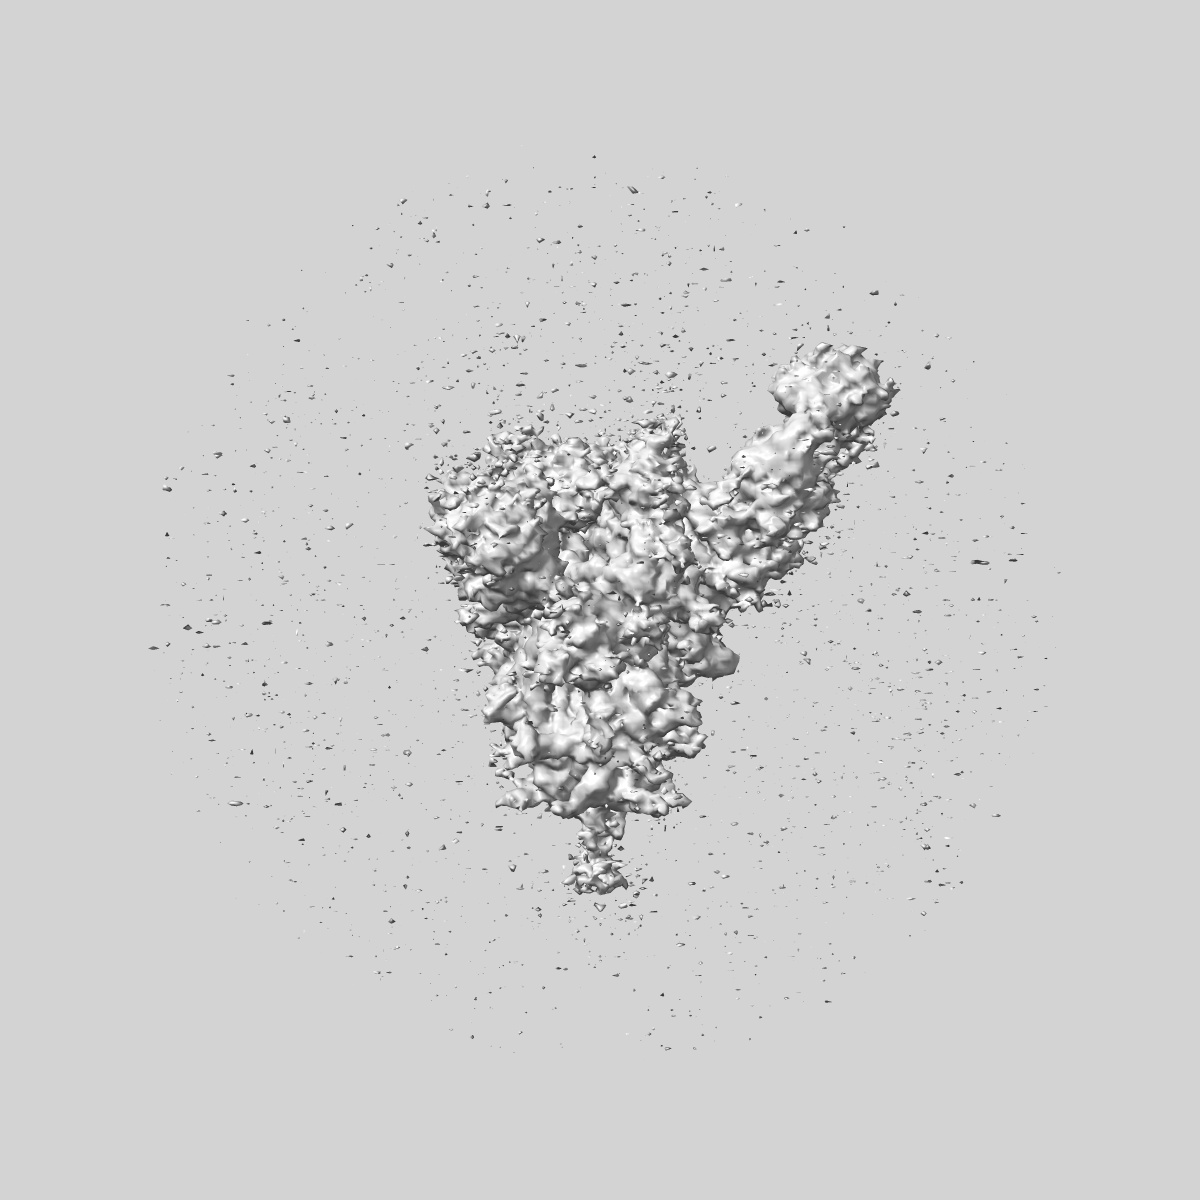

EMD-48201

SARS-CoV-2 Wuhan Spike ectodomain in complex with NHP polyclonal antibody NVX-NHPWu3 (NVX-CoV2373 vaccine)

Single-particle4.2 Å

Sample: SARS-CoV-2 Wuhan spike ectodomain in complex with NHP polyclonal antibody NVX-NHPWu3